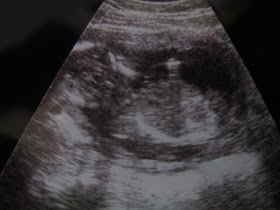

Yep, Baby W is the size of an Onion. I am sooooo excited. Last week I scheduled my Anatomy scan. April 12 we find out what the gender is, and take all those lovely measurements. The bad part...I have to drink 32 oz of water, and hold it for about an hour. Poor me!

How far along: 17.1 Weeks

Milestones: Baby is still kicking, and about 5 inches in length. Crazy how much they grow from week to week.

Baby's skeleton is hardening, changing from rubbery cartilage to bone, and fat is finally accumulating around it. The umbilical cord is getting thicker and stronger, and those little fingers and toes are now topped by one-of-a-kind prints.